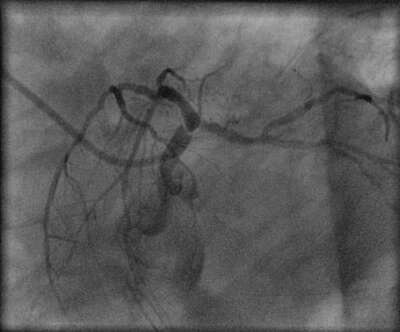

On the basis of elevated troponin I diagnosis of non-ST segment elevation myocardial infarction was made. The patient underwent cardiac catheterization and coronary angiogram which showed 90-95% left main coronary artery stenosis, 90% LAD, 95 % LCx, 90% marginal branch and 98 % dominant RCA stenosis with collaterals from the left system ( two representative views of left coronary artery are presented). There was severe left ventricular systolic dysfunction.

Stenosis left main image 2